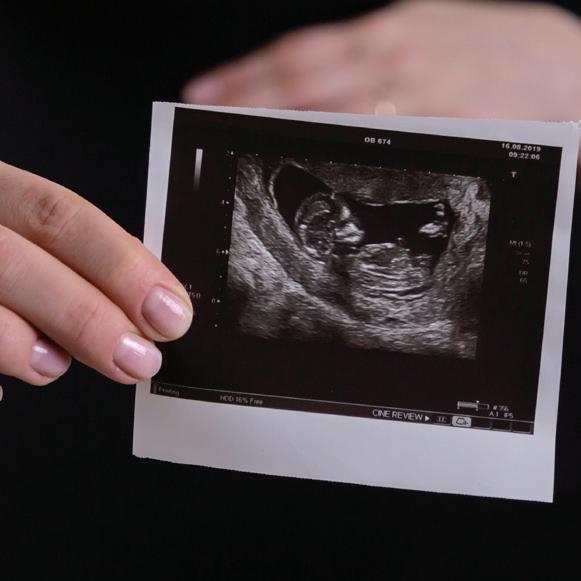

Am I Pregnant?

Pregnancy tests are not always accurate. Protect your health and get your pregnancy confirmed with an ultrasound. It can show if the baby is in the uterus and has a heartbeat and how far along you are. Going through an abortion without knowing this is risky.

A significant number of early pregnancies end on their own in miscarriage and a smaller number grow in the wrong place-outside of the uterus, which can be life-threatening.4 An ultrasound exam can confirm that your pregnancy is in the uterus and is living. This information is helpful as you make this decision: abortion or continuing with your pregnancy.

Any woman considering the abortion pill should have an ultrasound examination to verify if there is a pregnancy inside the uterus, see if there is cardiac activity, and obtain an estimate of gestational age. Without this critical evaluation, the risk of complications increases significantly.